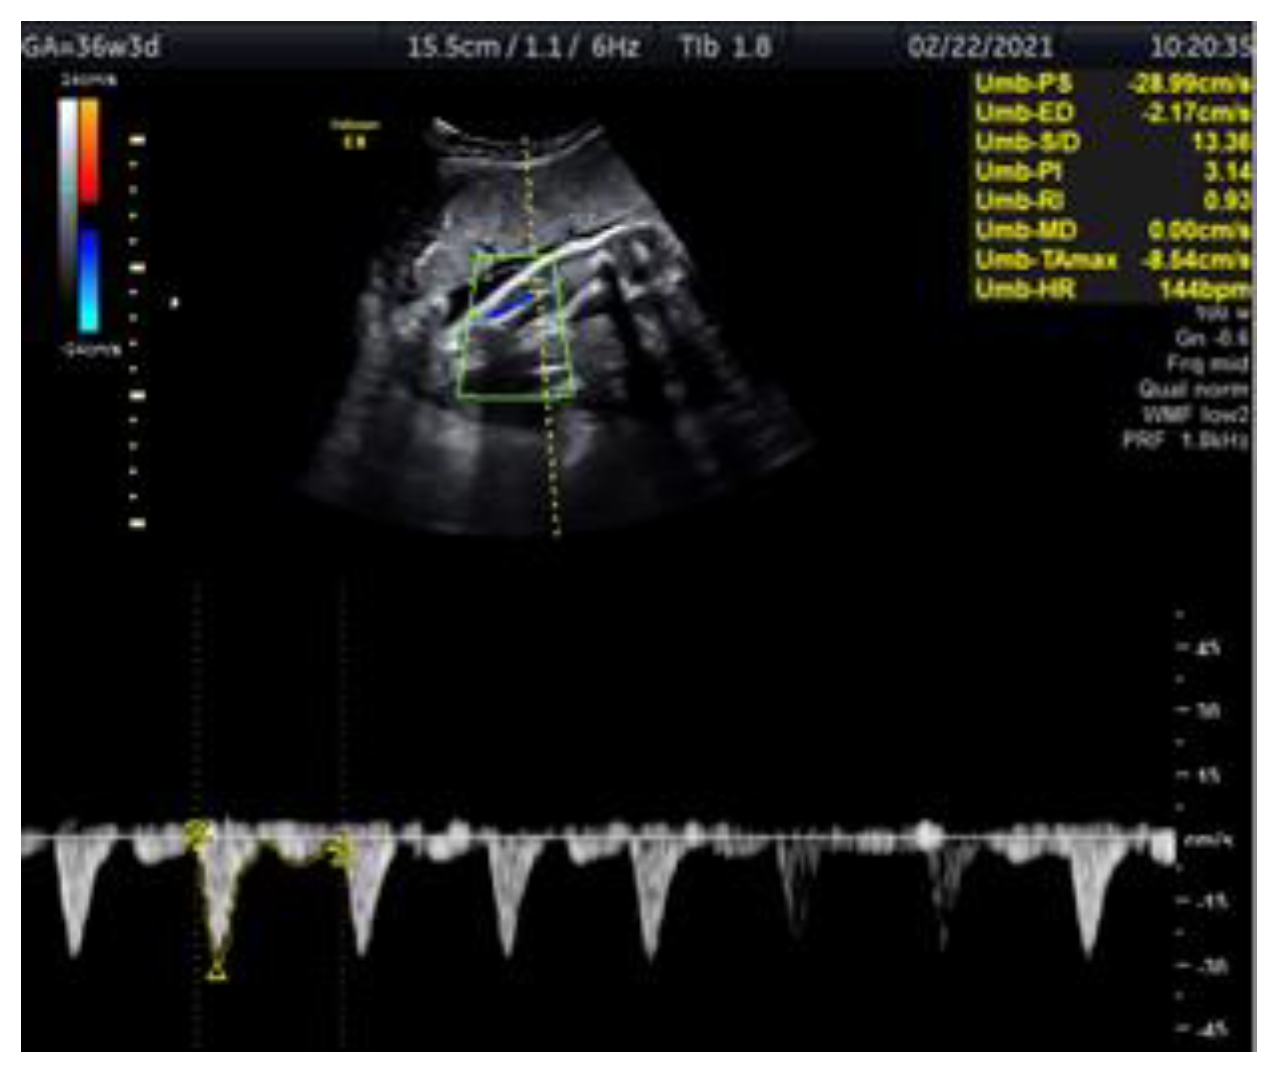

Doppler Ultrasonography of the Fetal Tibial Artery in High-Risk Pregnancy and Its Value in Predicting and Monitoring Fetal Hypoxia in IUGR Fetuses

2. Case Report